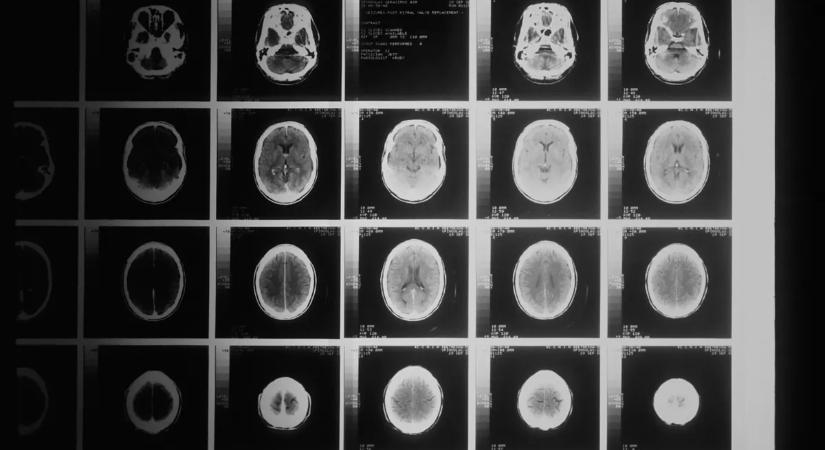

"Fáj a fejem attól, hogy nevetek, mert az agyam kiesik a helyéről"

Az orvosok több mint 14 éven át nem foglalkoztak tüneteivel.